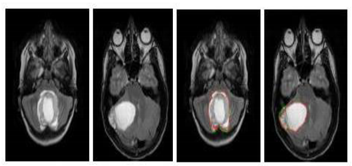

- Watershed line: it interprets an image as a height profile, flooded from regional minima so that, the lines where the flooded areas touch represent the watersheds [99,100]. It makes it possible to use the a priori knowledge of the clinician and his intervention, which facilitates visual evaluation in the higher level. However, it is difficult to implement and slow from a calculation point of view. In addition, the over-segmentation of images is generally frequent.